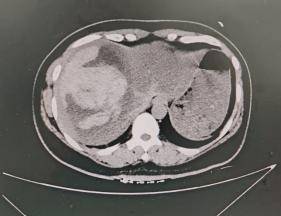

正在加班的介入中心李建军主任看过患者影像资料(图一)后,明确诊断患者肝出血,必须立即手术!然而,一个棘手的问题摆在面前:患者正处于月经期,介入栓塞术后再次出血和感染的风险会显著增高。但如果不紧急手术,一旦肝包膜下出血破裂,患者将很难存活。在与家属充分沟通、综合权衡利弊后,急诊介入栓塞术被确定为挽救段女士生命的唯一最优选择。与此同时,导管室的医护团队在崔雄伟主任和井学敏护士长的统筹安排下,宋丽波护士及杜宁技师已紧急就位,术前准备工作紧锣密鼓、有条不紊地推进。

(图一:患者术前 CT 影像(2025-11-16))